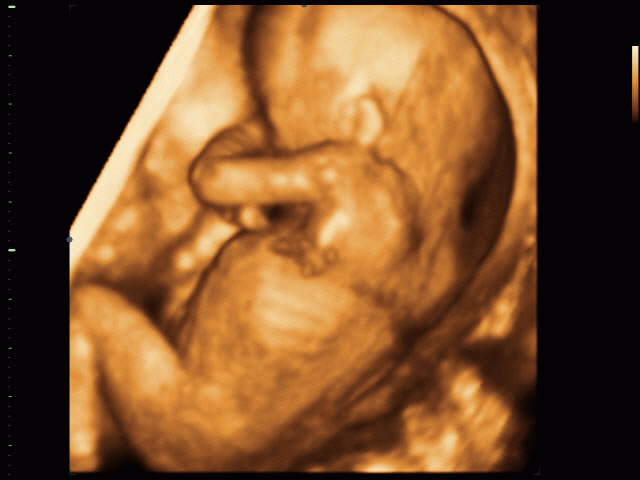

Ultrason uygulamasını fetal ve normal dönemde yapan yerleri nerede bulabilirim hastaneler görüntüleme merkezleri ve doktorlar muayenelerinde yapmaktadır. İstanbul da nerede detaylı ve ayrıntılı 4 boyutlu ultrason çektirmek gerekiyor sorusuna yanıtlar vereceğimiz bu yazımızda özel hastaneler olarak birçok bilgiye yer vereceğiz. Rad dr mehmet özer tarafından kurulan merkezimiz teknolojisini sürekli yenileyerek ve bilimsel gelişmeleri takip ederek hizmet vermektedir. Renkli doppler ultrasonografi yine ses dalgaları kullanarak damar yapıları içindeki akımı değerlendiren bir ultrason yöntemidir.

4 boyutlu ultrason merkezleri i̇stanbul. Dijital röntgen dijital panoromik röntgen dijital sefalometrik röntgen 3 boyutlu dental volümetrik tomografi dijital mammografi kemik yoğunluğu ölçümü ultrasonografi 4 boyutlu renkli doppler ultrasonografi departmanlarımızla hizmet vermekteyiz.